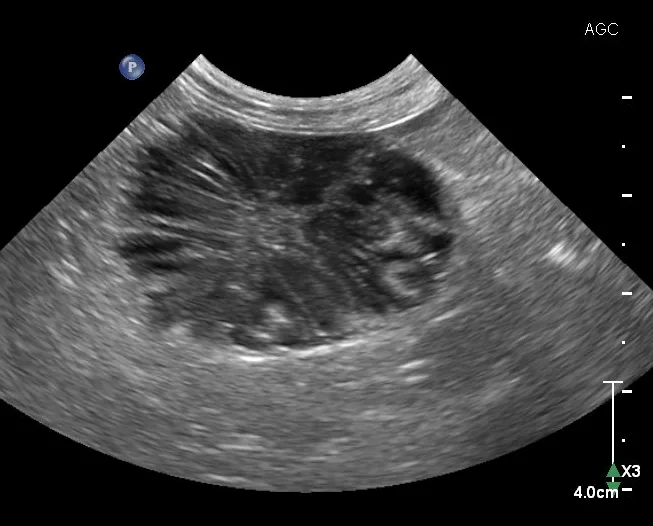

1. Urinary Bladder Evaluation & Cystocentesis

Cystocentesis allows sterile collection of urine while avoiding the potential complications of manual bladder compression, urethral catheterization, or contamination from free-flow collection.4 Ultrasound guidance can help decrease risk of unintentionally inserting the needle into nearby structures (eg, colon, caudal vena cava, descending aorta) and allows for brief assessment of the urinary bladder. Although some pathologic changes in the urinary bladder (eg, mild cystitis) can be subtle and easily overlooked, other diseases can be very apparent. Cystic calculi can range in shape and size but, when large enough, may have a hyperechoic interface that causes a distal acoustic shadow (Figure 1). In patients with hematuria, blood clots with different shapes can float in the urine or rest dependently against the bladder wall. Neoplasia of the urinary bladder can differ in visualized size and echogenicity; however, neoplasia typically originates from the bladder wall, demonstrates irregular margins, and protrudes into the bladder lumen. If a mass is identified in the urinary bladder, cystocentesis is not recommended to prevent potential seeding of neoplastic cells in the soft tissue along the path of the needle.

FIGURE 1

Sagittal image of the urinary bladder (UB; cranial aspect toward the left side of the image). Numerous calculi (between calipers) are present along the dependent aspect of the urinary bladder (away from the probe with the patient in dorsal recumbency) and, unlike in cases of neoplasia, are hyperechoic and cast a clean acoustic shadow.